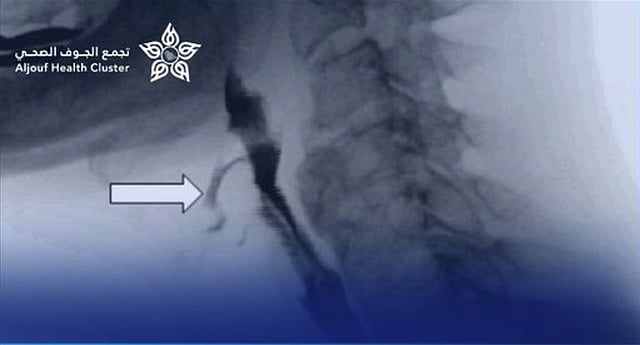

نجح فريق طبي متخصص من قسم الجهاز الهضمي للأطفال وقسم التخدير بمستشفى الملك عبد العزيز التخصصي بالجوف، بالتعاون مع مستشفى النساء والولادة والأطفال، في إجراء عملية توسيع للمريء بالمنظار لطفل يبلغ من العمر 11 عامًا، دون الحاجة إلى أي تدخل جراحي.

وأوضح التجمع الصحي بمنطقة الجوف أن الطفل كان يعاني من صعوبة شديدة في البلع واسترجاع متكرر للطعام، وتبيّن بعد الفحوصات وجود تضيق شديد في المريء يعيق مرور الطعام. وقد قام الفريق الطبي بإجراء عملية توسيع للتضيق باستخدام المنظار والموسعات الطبية المناسبة، تكللت بالنجاح الكامل دون أي مضاعفات.

وأشار التجمع إلى أن حالة الطفل تحسّنت بشكل ملحوظ بعد العملية، وتمكن من تناول الطعام بصورة طبيعية، وغادر المستشفى بعد يومين من الإجراء وهو في صحة جيدة.